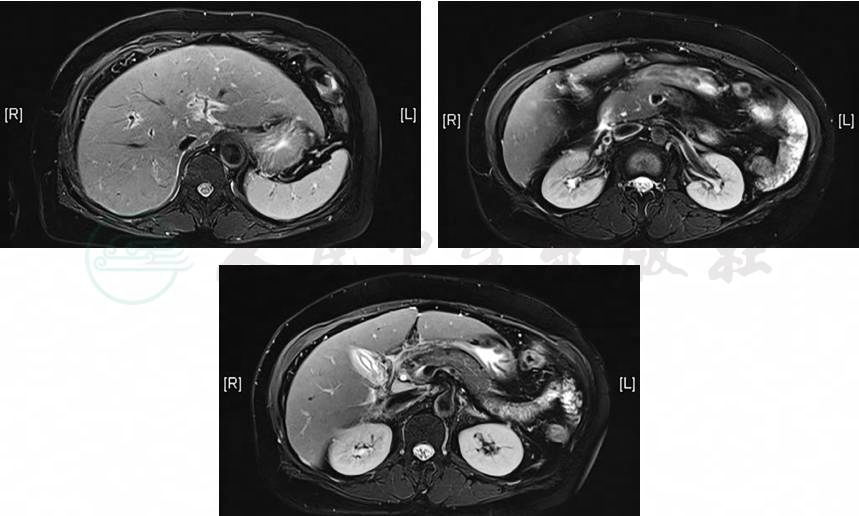

2019-12-27肝脏MRI平扫+增强+MRCP(图1):肝稍大且信号不均匀,炎性病变所致可能;急性胆囊炎,肝内外胆管及胰管未见明显异常;胰腺头部及尾部稍饱满;扫描野右肾双肾盂双输尿管重复畸形。骨髓片检查:浆细胞比例升高,形态无异常。

图1 MRCP